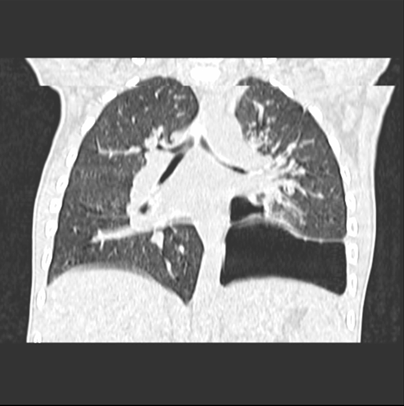

We asked for a Chest CT scan